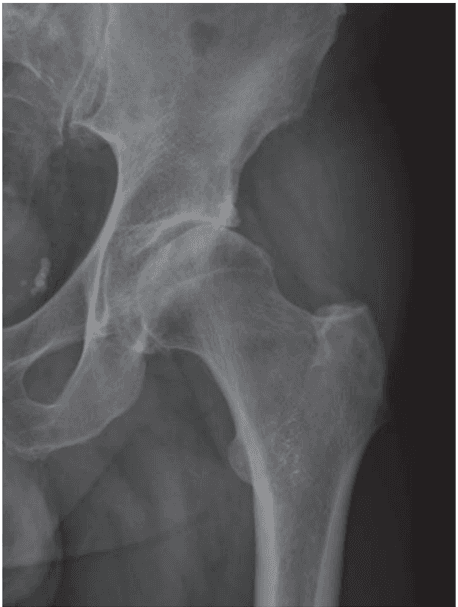

Is intra-articular injection of autologous micro-fragmented adipose tissue effective in hip osteoarthritis? A three year follow-up

Adipose-Derived Stem Cells for Hip Osteoarthritis: A Promising Case Series

Micro-fragmented Adipose Tissue Transplantation (MATT) for the treatment of acetabular delamination. A two years follow up comparison study with microfractures

Mesenchymal Stem Cells injection in hip osteoarthritis: preliminary results